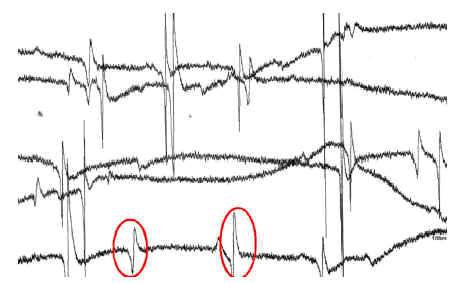

Paciente de 72 años de edad ingresado en Unidad de Cuidados Intensivos (UCI) con insuficiencia respiratoria global por una reagudización de enfermedad pulmonar obstructiva (EPOC). El paciente tiene dificultades para la desconexión de la ventilación mecánica por atelectasias de repetición y acidosis respiratoria grave. En la figura 1 se observa la radiografía de tórax en ventilación mecánica y en la figura 2 una de la imágenes de atelectasia al reducir el soporte ventilatorio. Se realizó electromiograma de diafragma mediante punción del pilar anterior por acceso retroesternal, en el que aparecieron datos de denervación (fibrilaciones y ondas rítmicas de denervación "marcadas con un circulo rojo") (fig. 3). El paciente fue dado de alta de UCI y del hospital con soporte ventilatorio parcial.

Figura 3.